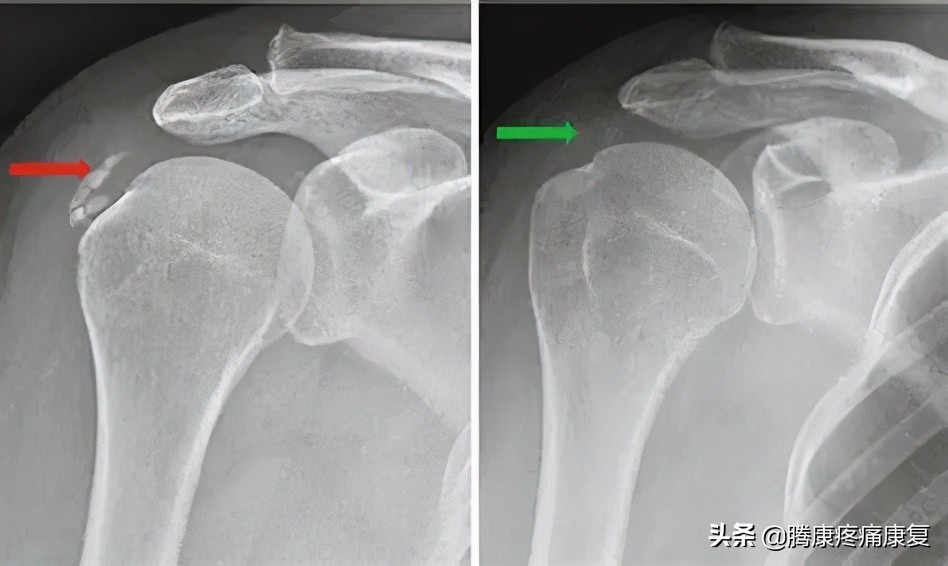

急性肩关节病变可能与肩袖肌腱钙化相关。在出现疼痛以前,钙化可能已存在数年而没有症状,伴有钙质吸收。这一过程可能影响肩关节活动度和生活质量,但是其自然病程往往会自然恢复。钙化性肌腱炎可能较少见于手部、前臂和下肢的其他肌腱。

- 再吸收期 特征为持续数周的严重疼痛和活动受限。再吸收过程中的钙质释放将导致半固体物质外渗。羟基磷灰石结晶释放入软组织和肩峰下滑囊,将引起刺激和炎症反应,导致疼痛。

- 在 钙化后期 过程中出现肩袖愈合和修复。某些患者疼痛可能持续数月,影响功能。钙化最常累及冈上肌肌腱,随后是冈下肌肌腱,小圆肌肌腱和肩胛下肌肌腱。